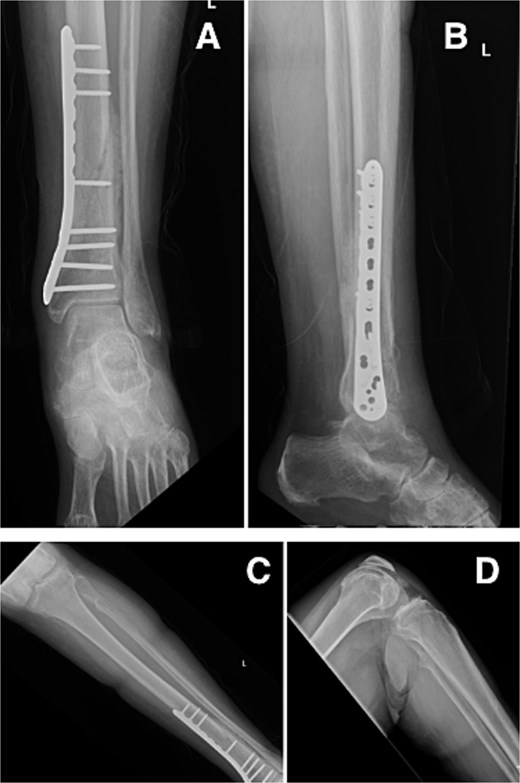

At our latest 3-month follow-up, the patient demonstrated appropriate clinical and radiographic healing of the distal tibial fracture without complication. Interval radiographs confirmed maintained alignment and progressive osseous union at the fracture site (Fig. 4).

Radiographs at 3-month follow-up demonstrating healing of the left distal tibial spiral fracture and associated proximal fibular fracture. (A) Anteroposterior and (B) lateral views of the distal tibia show maintained alignment and progressive osseous union. (C) Anteroposterior and (D) lateral views of the proximal fibula demonstrate interval fracture healing.